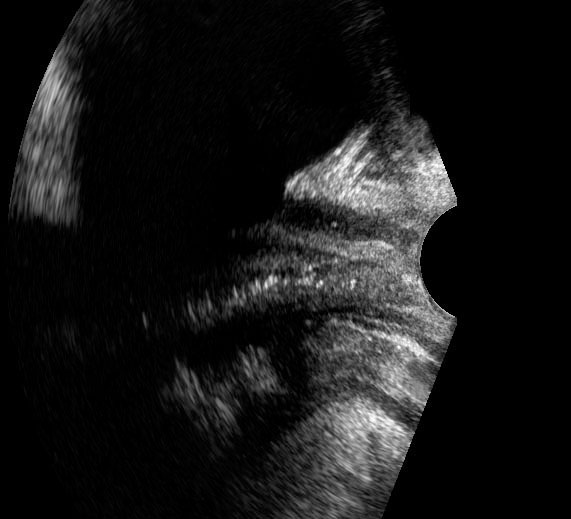

Bệnh lý của niệu đạo, âm đạo đoạn xa và cơ thắt hậu môn có thể được khảo sát bằng đầu dò âm đạo đặt ở vị trí âm hộ (mặt phẳng đứng dọc).

Hình ảnh

Giải phẫu siêu âm bình thường với đầu dò ở vị trí âm hộ